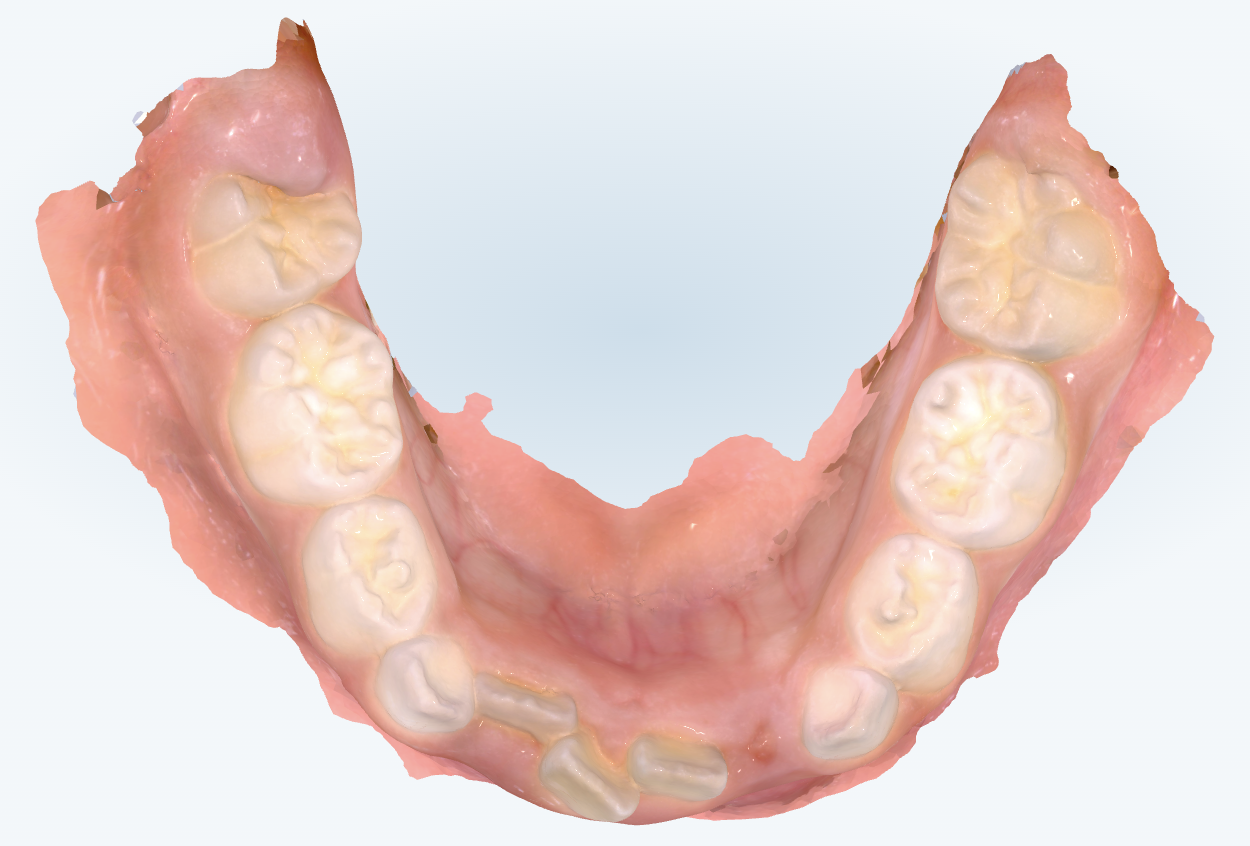

初診時の画像診断

上下の前歯の生え替わりがスタートしています。

下の前歯にガタつきがあります。

検査では、前歯部のスペースがやや不足し、上下歯列の弓形(アーチ)がやや狭いことがわかりました。

骨格的な大きなズレはなく、将来のガタガタ(叢生)を予防する“土台づくり”が最優先であると判断しました。